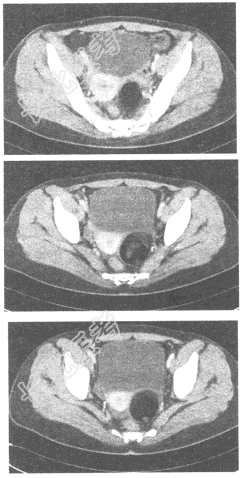

- 单项选择题女,35岁, 下腹部胀痛,CT扫描如图所示, 盆腔内囊实性肿块影,其内CT值不均, CT值-120~360HU不等,最可能的诊断是

A、子宫肌瘤

B、卵巢癌

C、卵巢畸胎瘤

D、卵巢囊肿

E、以上都不是